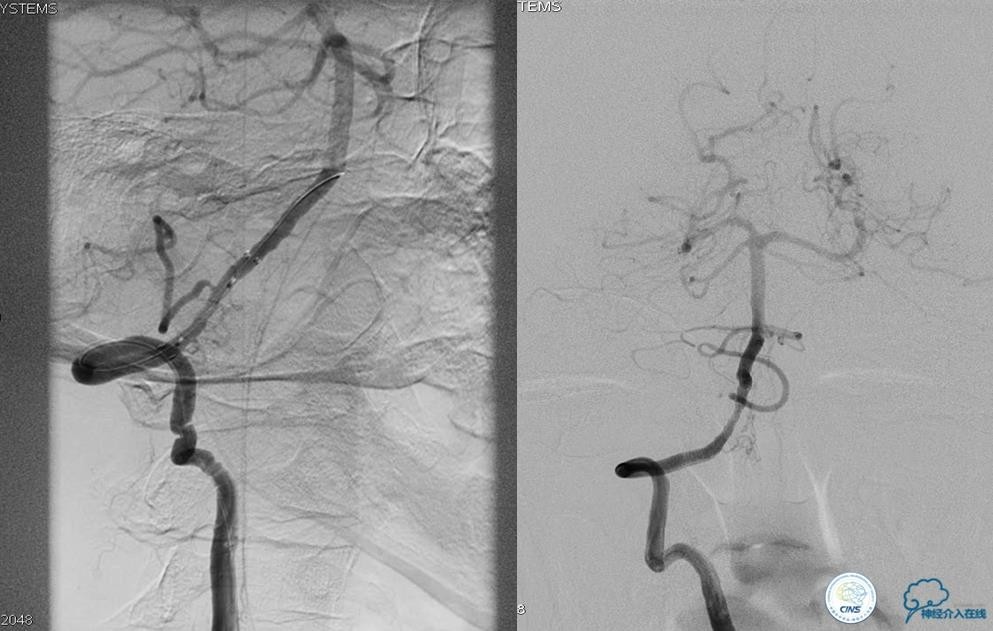

▼开通